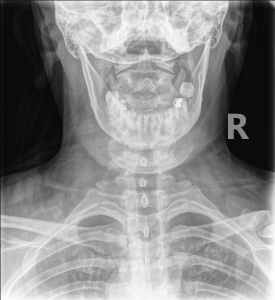

Fig. 1 AP cervical view

Fig. 2 AP cervical view showing red annotation highlights a nonunion fracture of the right clavicle.

If you didn’t scan the corners of your AP Cervical view, you likely missed the root cause: A non-union or mal-positioned clavicular fracture.

While a dedicated Clavicle Series (AP and Cephalic tilt/Zanca view) is ideal, you will often catch this incidentally on:

• AP Lower Cervical: Check the top corners of the film.

1. The Radiolucent Cleft: You will see a persistent black line or gap between the fracture fragments that does not bridge with bone.

2. Sclerotic Margins: The ends of the bone will look white, smooth, and “sealed off.” This indicates the body has “given up” trying to bridge the gap and has instead sealed off the medullary canals.

3. Absence of Bridging Trabeculae: Follow the trabecular lines. If they stop abruptly at the fracture site and do not cross over, union has not occurred.

4. Step-Off and Displacement: The medial fragment is almost always elevated (SCM pull), and the lateral fragment is depressed.